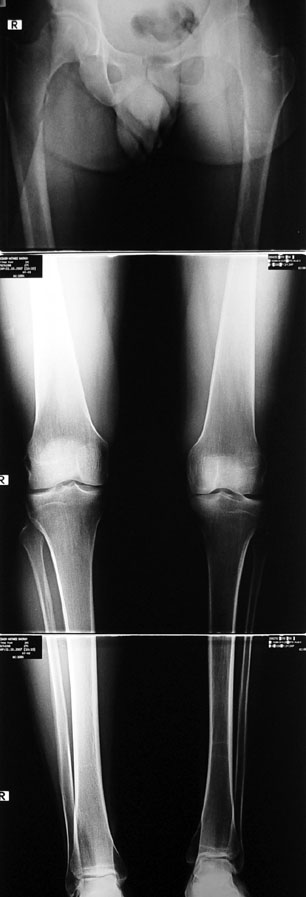

Shortness of the leg or thigh can occur due to various reasons. There are three main causes:

Congenital

Developmental (shortness which occured after birth due to a childhood disease which disrupted or

slowed down the growth plates)

Posttraumatic (fractures with bone loss)

Many patients don’t want to use a shoe support thicker than 2 cm. For length differences between 2 cm and 5 cm, shortening may be considered for tall patients. This can be performed in growing children with a small, minimally invasive, uncomplicated procedure called epiphysiodesis. This means surgical disruption of one or more growth plates. There is a growth plate at the ends of femur, tibia and fibula; this procedure does not halt all growing of the leg. The growing of the longer leg is calculated and halted to allow the shorter leg to catch up.If the procedure is performed at a too early or too late age, the correction may be too much or too little, respectively. Hence, it is important to accurately calculate the most appropriate age for epiphysiodesis. When and at which bone segment epiphysiodesis will be performed shall be calculated by the doctor using different methods such as Gren-Anderson diagram, Moseley curve or Paley’s multiplier method.Epiphysiodesis is not an option for adults because growth plates ar closed. In adults, a bone segment has to be excised surgically in order to shorten the leg. This is usually performed at femur and bone is later fixed with an intramedullary nail. The biggest advantage of this system is that it acutely provides limb length equality for discrepancies less than 5 cm. The common disadvantage of epiphysiodesis and shortening is the shortening of total height of the patient. Because we don’t advice shortening more than 5 cm, height loss can’t be more than 5 cm. For patients who don’t want an epiphysiodesis or shortening operation for length inequalities less than 5 cm, limb lengthening can be preferred in order to equalize the length difference.This can be combined with epiphysiodesis and shortening to decrease a need for another lengthening operation or to decrease the lengthening amount required.

1. CONGENITAL LOWER LIMB SHORTNESS

Patients with congenital lower limb shortness are hard cases who should be treated by surgeons experienced in lenghtening of developmental and posttraumatic lower limb shortness. Not only the amount of shortness is big but also it increases gradually and proportionately in time. A method to increase the growing rate of a short leg is not known. In addition to bone shortness, the soft tissues are thick and short, and they hinder lengthening by stretching. Development of the hip, knee and/or ankle joints may be insufficient and/or the joints may be instable. All of these factors shall be evaluated carefully to avoid irreversible damage in the joints, nerves and muscles. All cases of congenital lower limb shortness are treated in our department. In the beginning, we calculate how much length discrepancy there will be after skeletal maturity is gained. After all deformities and joint instabilities have been defined, the treatment stategy is organized for the limb, including the surgical correction of the hip, knee, ankle and foot. Lengthening surgery may involve one or more operations. Most of the patients with congenital lower limb shortness can be treated by lengthening and reconstruction. For most cases, we prefer to start lengthening and reconstruction procedures before the patient is 4 years old, usually before 2 years of age. An alternative treatment method is amputation so that the limb fits more easily in a prosthesis, and lengthening of the prosthesis with growing of the child in order to correct limb length inequality. We call this procedure prosthesis reconstruction surgery (PRS), and includes operations like Syme amputation and Van Ness rotationplasty. While this procedure may be the best choice for those patients with serious defects lacking one or more joints, in our opinion it is not the best choice fort he majority of patients. Our results for femur and tibia lengthening are perfect even for very big length differences, and perfect results are achieved in development and maintenance of joint functions.

2. DEVELOPMENTAL LOWER LIMB SHORTNESS

This includs lower limb shortness which occurs following growth plate disruption and growth arrest, Ollier’s Disease, multiple osteochondomatosis, poliomyelitis, infection, radiation (radiotherapy), cerebral palsy, spina bifida, club foot and similar disorders. Additional abnormalities are frequent in this group. Many cases can be treated with one or two lengthening operations. If present, deformity can be corrected simultaneously with shortness. For condirtions that damage the hip joint at the first year of life like neonatal sepsis, we reconstruct the hip joint with pelvic support osteotomy in addition to lengthening, and a hip joint with nearly normal function is acquired.

3. POSTTRAUMATIC LOWER LIMB SHORTNESS (MALUNION)

This type of shortness occurs after a fracture heals in a shortened position. Most cases are seen in adults and can be treated with one lengthening operation. Additional deformities can be corrected simultaneously. Most of these cases can be treated with lengthening over nail or just corrections and intramedullary nailing.